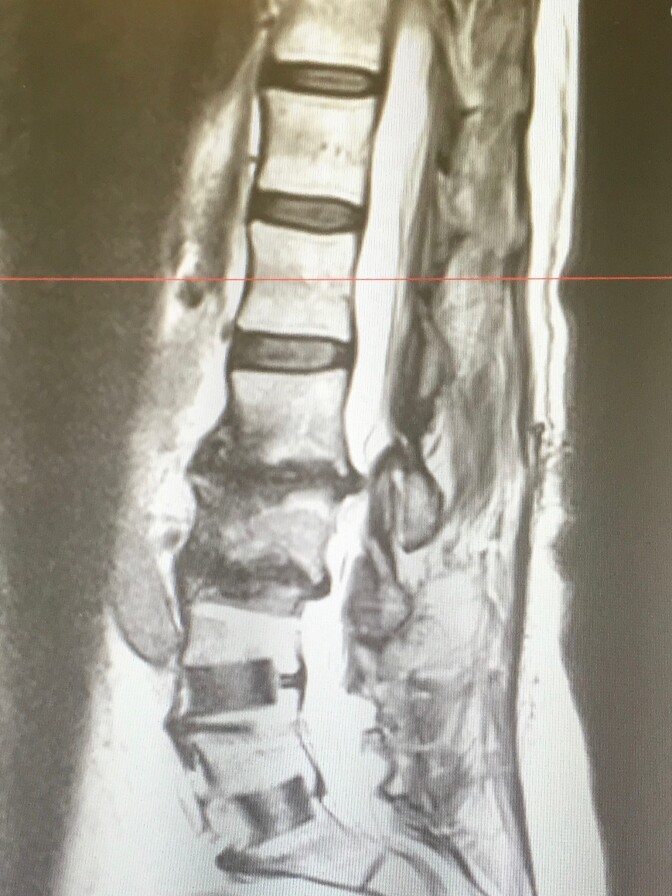

By her mid-50s, she had two back surgeries and both her hips replaced.

Germanovich says he sees lots of patients like Curtis, middle-aged men and women whose bodies are naturally deteriorating. He says it’s no wonder that middle-aged people are dying of opioid overdoses at the highest rates in California. They’re the ones most in need of pain relief.

"Degenerative neck and back disease typically starts to come right after the age of 45," he says, "and doesn't manifest itself in big ways until someone is almost 50."

Last year, Curtis had yet another surgery, this time for degenerative disc disease. It has given her some relief. Since that surgery, Germanovich has been helping her taper off opioid pain relievers.